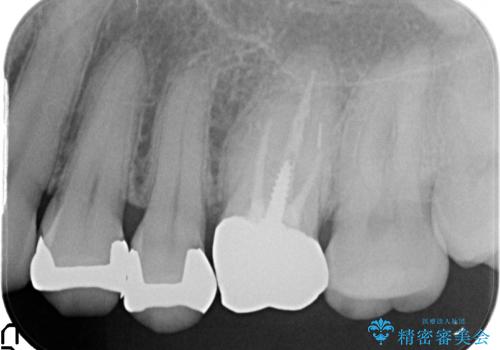

- 左上4、5、6番目の歯を白くしたいといらっしゃった方の症例です。

4番目の歯はセラミックインレーによる修復、5・6番目の歯はオールセラミッククラウンによる補綴を行いました。

左上6番目の歯については再根管治療を行っております。